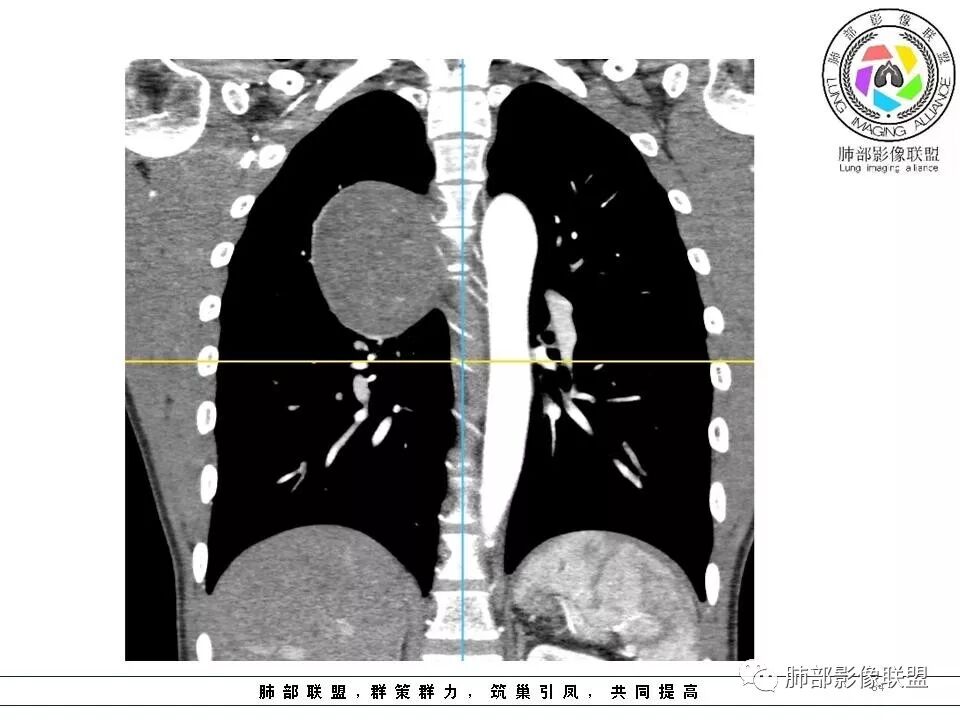

右肺占位,跨越上叶后段、下叶背,边缘光滑,瘤肺界面清,见肺压缩缘(线样不张`强化),见胸膜尾征,胸膜下脂肪未见明显增厚,肋骨丶脊柱未见侵袭及受压,渐进性丶地图样强化,冠状位似见体循环供血

右上肺野脊柱旁软组织肿块,边缘光滑整齐,肺组织及气管右肺上叶支气管受压前移,外移,边缘可见胸膜尾征,病灶内密度不均,增强后渐进性持续强化,其内可见明显蛇纹血管征,首先考虑肺外来源,sft.可能性大

青年男性,右侧脊柱旁占位,瘤肺界限清晰,支气管推移,胸膜尾,D字征,胸膜下脂肪影,蛇纹血管,双重供血,延迟强化,定位胸膜,支持sft

右侧肺脊柱旁肿物,密度均匀,边缘清晰,宽基底与脊柱相贴,少量胸水挤压,增强明显强化,内见蛇纹征,与胸壁未见脂肪,定位肺外,定性SFT ,鉴别神经源性

右侧脊柱旁肿块,边界清晰,密度稍欠均匀,宽基底与胸膜相贴,脂肪间隙消失,见胸膜尾征,增强有强化,见蛇纹血管,定位胸膜,考虑SFT(孤立性纤维瘤)。

青年男性,瘤肺边界锐利,气管向前推移,定位肺外,局部胸膜增厚,后方见少量积液,提示脏层胸膜来源,增强持续渐渐进性强化,内见蛇纹血管,考虑sft

边缘光滑,宽基底与胸壁相连,跨叶裂,叶裂稍前推,血管、支气管前移。

浅分叶

外上侧少量胸水

肋间动脉供血,强化尚均匀,逐步强化

这个病变看着外面是胸膜模糊的改变,但是血管是从椎间孔过来的,这个胸膜外缘有个间隙存在,个人觉得神经鞘瘤等不能排除。胸膜尾这个征象,外面一层增厚的、延迟第2、3期的局部似乎与肿瘤有间隙,所以不是很踏实。淋巴瘤不太考虑,形态不符,贴在附近软组织梭形改变,有血管进入,当时怀疑淋巴瘤,是上面有个强化的地方不放心。

供血,体外供血,体循环,要么是壁层胸膜,要么胸膜外的,脏层胸膜应该是对内供血。病变里面的血管,除非是非常粗大迂曲的血管,不然,我不认为是其特点。

如果一个大的病变,无论胸膜腔内、还是外,它都会将液体局部阻断,因为太大会把局部隆起,胸膜局部推压,哪一方面推压都会阻断。如果幸运看到里面的积液,积液可见渗入到附近间隙,如果在肿块后面肯定是胸膜腔内,在前面,要么是壁层胸膜,要么胸膜外的。

这个胸膜间隙,看起来就是一个脏层胸膜一个壁层胸膜,来源就很多种,胸膜是弧形,不规则半圆,后方的、外侧的、内侧纵隔胸膜、肋胸膜,病变来源很多种,第1肺内的,第2脏层胸膜的,胸壁的、肋间的神经源性。例脏层胸膜的,胸膜本身宽基的,带蒂的朝肺内、带蒂的朝胸膜腔突出的,这些都有差异,壁层胸膜也是。胸膜尾征这个有多大价值,贴近胸膜的病变,压迫、刺激胸膜局限性增厚,我对胸膜尾征价值不踏实,我觉得对胸膜的推移对病变对病变定位反而有价值,好就好在这个区域的病变不多,良性的有推移,恶性的有侵袭性特点,肋骨来源、附近的肉瘤,神经源性肿瘤恶变,间叶组织来源,转移瘤,还有就是全身疾病免疫、血液来源的,我觉得定到胸膜外、如果能定胸膜就定,定不到就定不到,如果是肺内动脉血供,与肺没有关系,定在胸膜,孤立性纤维瘤常见,鞘瘤等罕见。

1.右上胸内脊柱旁类圆形肿块,质地似乎比较坚实,密度稍显不均,但未显示明确的坏死。

2.肋间动脉病供血也提示肿块来自后纵隔?

3.相邻椎间孔未见扩大,也未见块影延入椎管,易起自于神经根的鞘瘤似乎找不到支持点。

可惜未提供矢状位骨窗图像,如在肋骨内下缘观察到压迹有助于肋间神经的鞘瘤的判断,这是因为二者之间密切的毗邻关系。